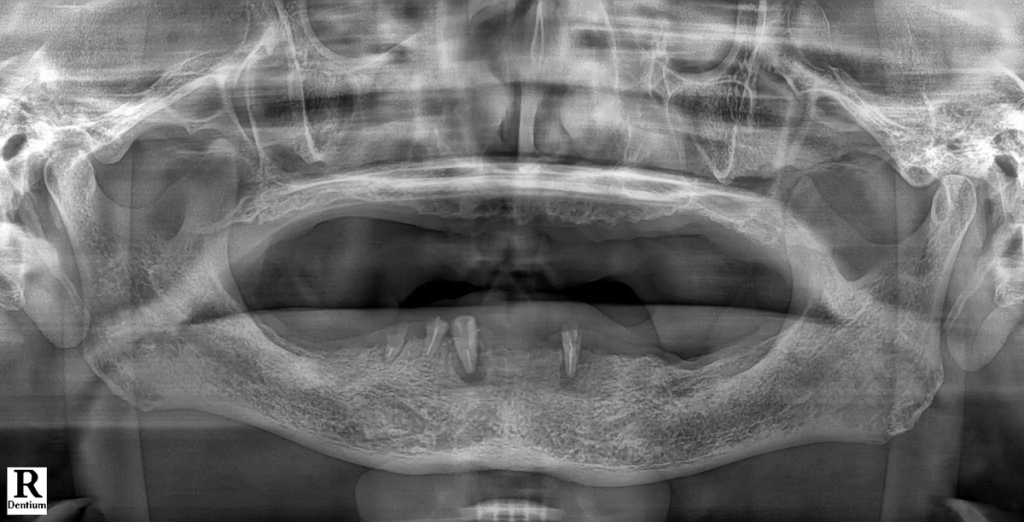

Case 3. 사고 후 뼈 부족으로 치료를 고민하던 40대 남성

이 환자분은 사고로 여러 개의 치아를 상실했고, 잇몸뼈가 많이 부족한 상태였습니다. 일반 임플란트를 하려면 뼈이식과 긴 회복 기간이 필요하다는 말을 듣고, 치료를 망설이고 계셨습니다.

- 디지털 풀아치 임플란트를 선택한 이유 상담 과정에서 디지털 풀아치 임플란트는 상대적으로 단단한 뼈 부위를 활용해 식립하기 때문에, 광범위한 뼈이식 없이도 치료할 수 있다는 설명을 들었습니다. 디지털 스캐닝과 시뮬레이션을 통해 환자분의 구강 상태에 맞춘 맞춤형 치료 계획이 세워졌고, 이를 바탕으로 치료를 결심하게 되었습니다.

- 치료 후 변화 “치아 때문에 받던 스트레스가 사라졌고, 일상생활로 빠르게 돌아갈 수 있었습니다.” 디지털 가이드를 활용한 수술로 치료가 진행되었고, 생각보다 짧은 기간 안에 치료가 마무리되었습니다. 환자분은 빠른 회복 속도에 만족감을 보였으며,